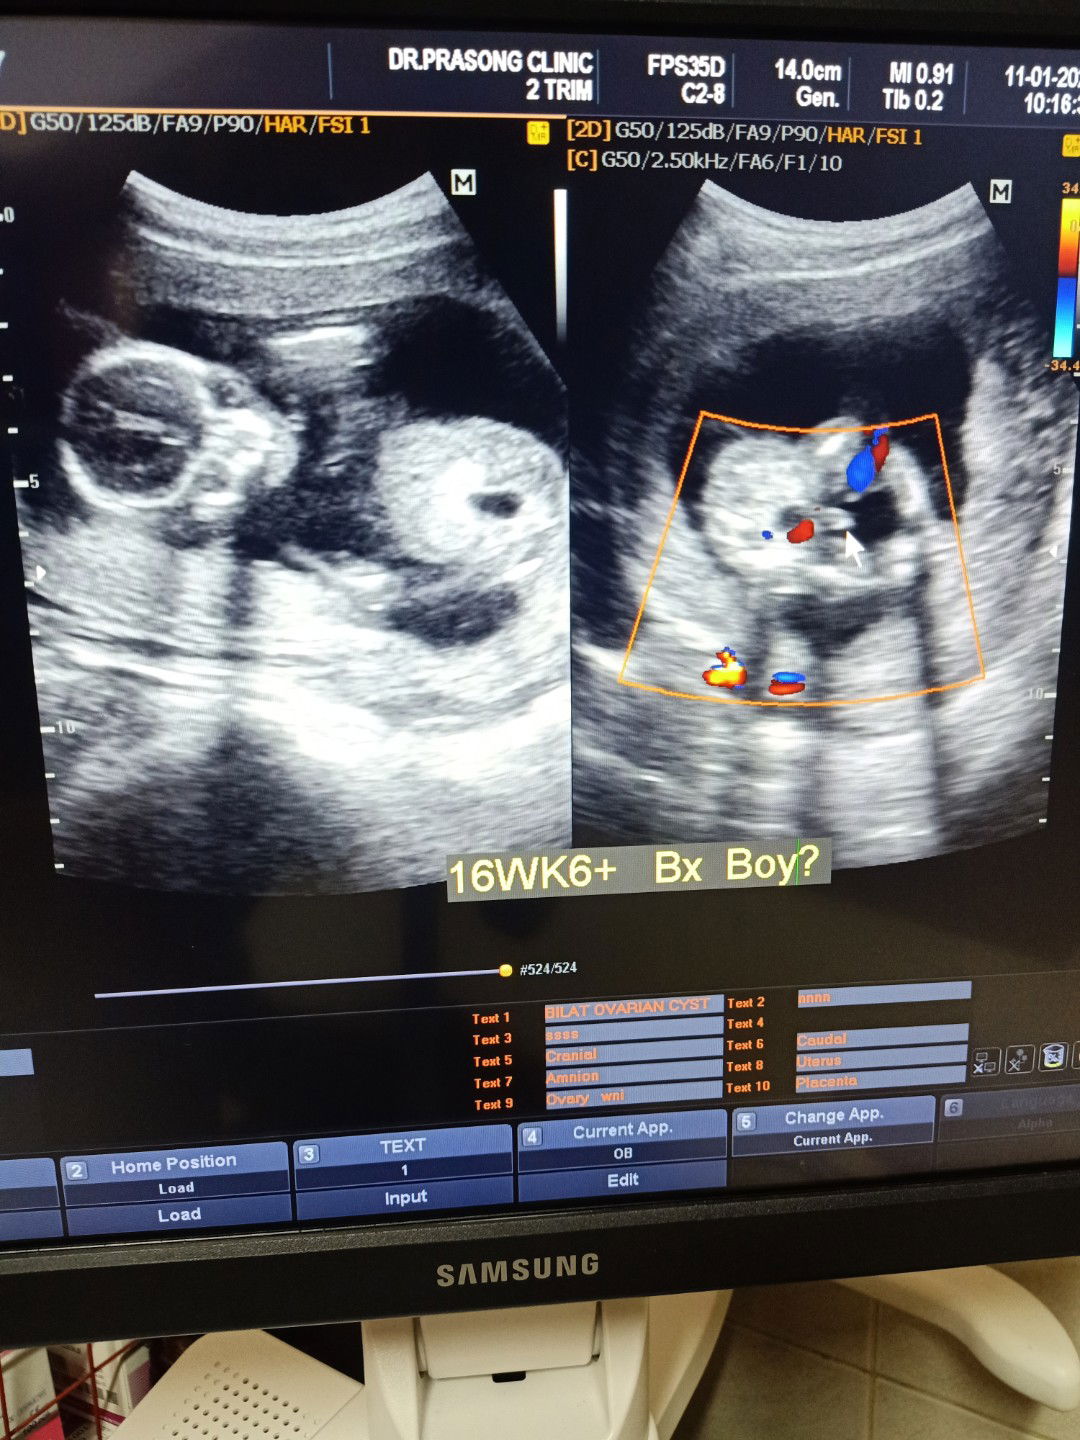

บ้านนี้ได้ ผช ค้า?

วันนี้น้อง16 วีค+6เเล้ว เเข็งเเรงดีค่ะ ตัวใหญ่มากเเม่ๆบ้านอื่นเป้นไงบ้างค้ะ ผลที่หมอดูรอบนี้ ผช ค้า?

ซาวครั้งไหนๆตื่นเต้นทุกทีค้ะ#รออยากเจอน่าเเล้ว?